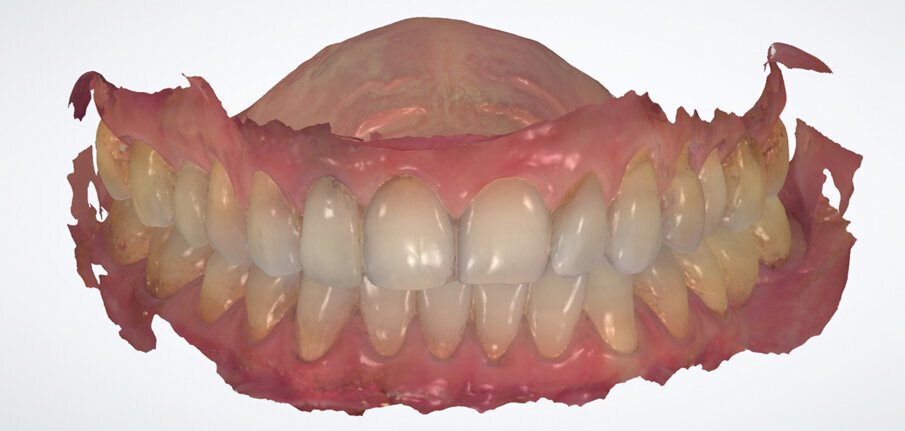

Fig. 3. Surface scan of the preoperative situation

Fig. 6. Surface scan of the preoperative situation

This method ensures the accuracy of the restoration procedure. The transgingival areas have already been formed at the time of the temporary restoration. In the present case, the thickness of the gingival tissue should be additionally increased. For the final restoration, a Ti base of the same length as the one for the temporary restoration is used. This time, however, the base features an anti-rotation lock. A large selection of materials is available for the final restoration. We normally use hybrid restorations for the restoration of single implants. Here, the restoration consists of a monolithic zirconium oxide abutment (Zenostar) and a monolithic multi-shaded all-ceramic crown (IPS e.max ZirCAD MT Multi). The restoration is characterized with stains and completed without any shape modifications (Figs 14 to 16).